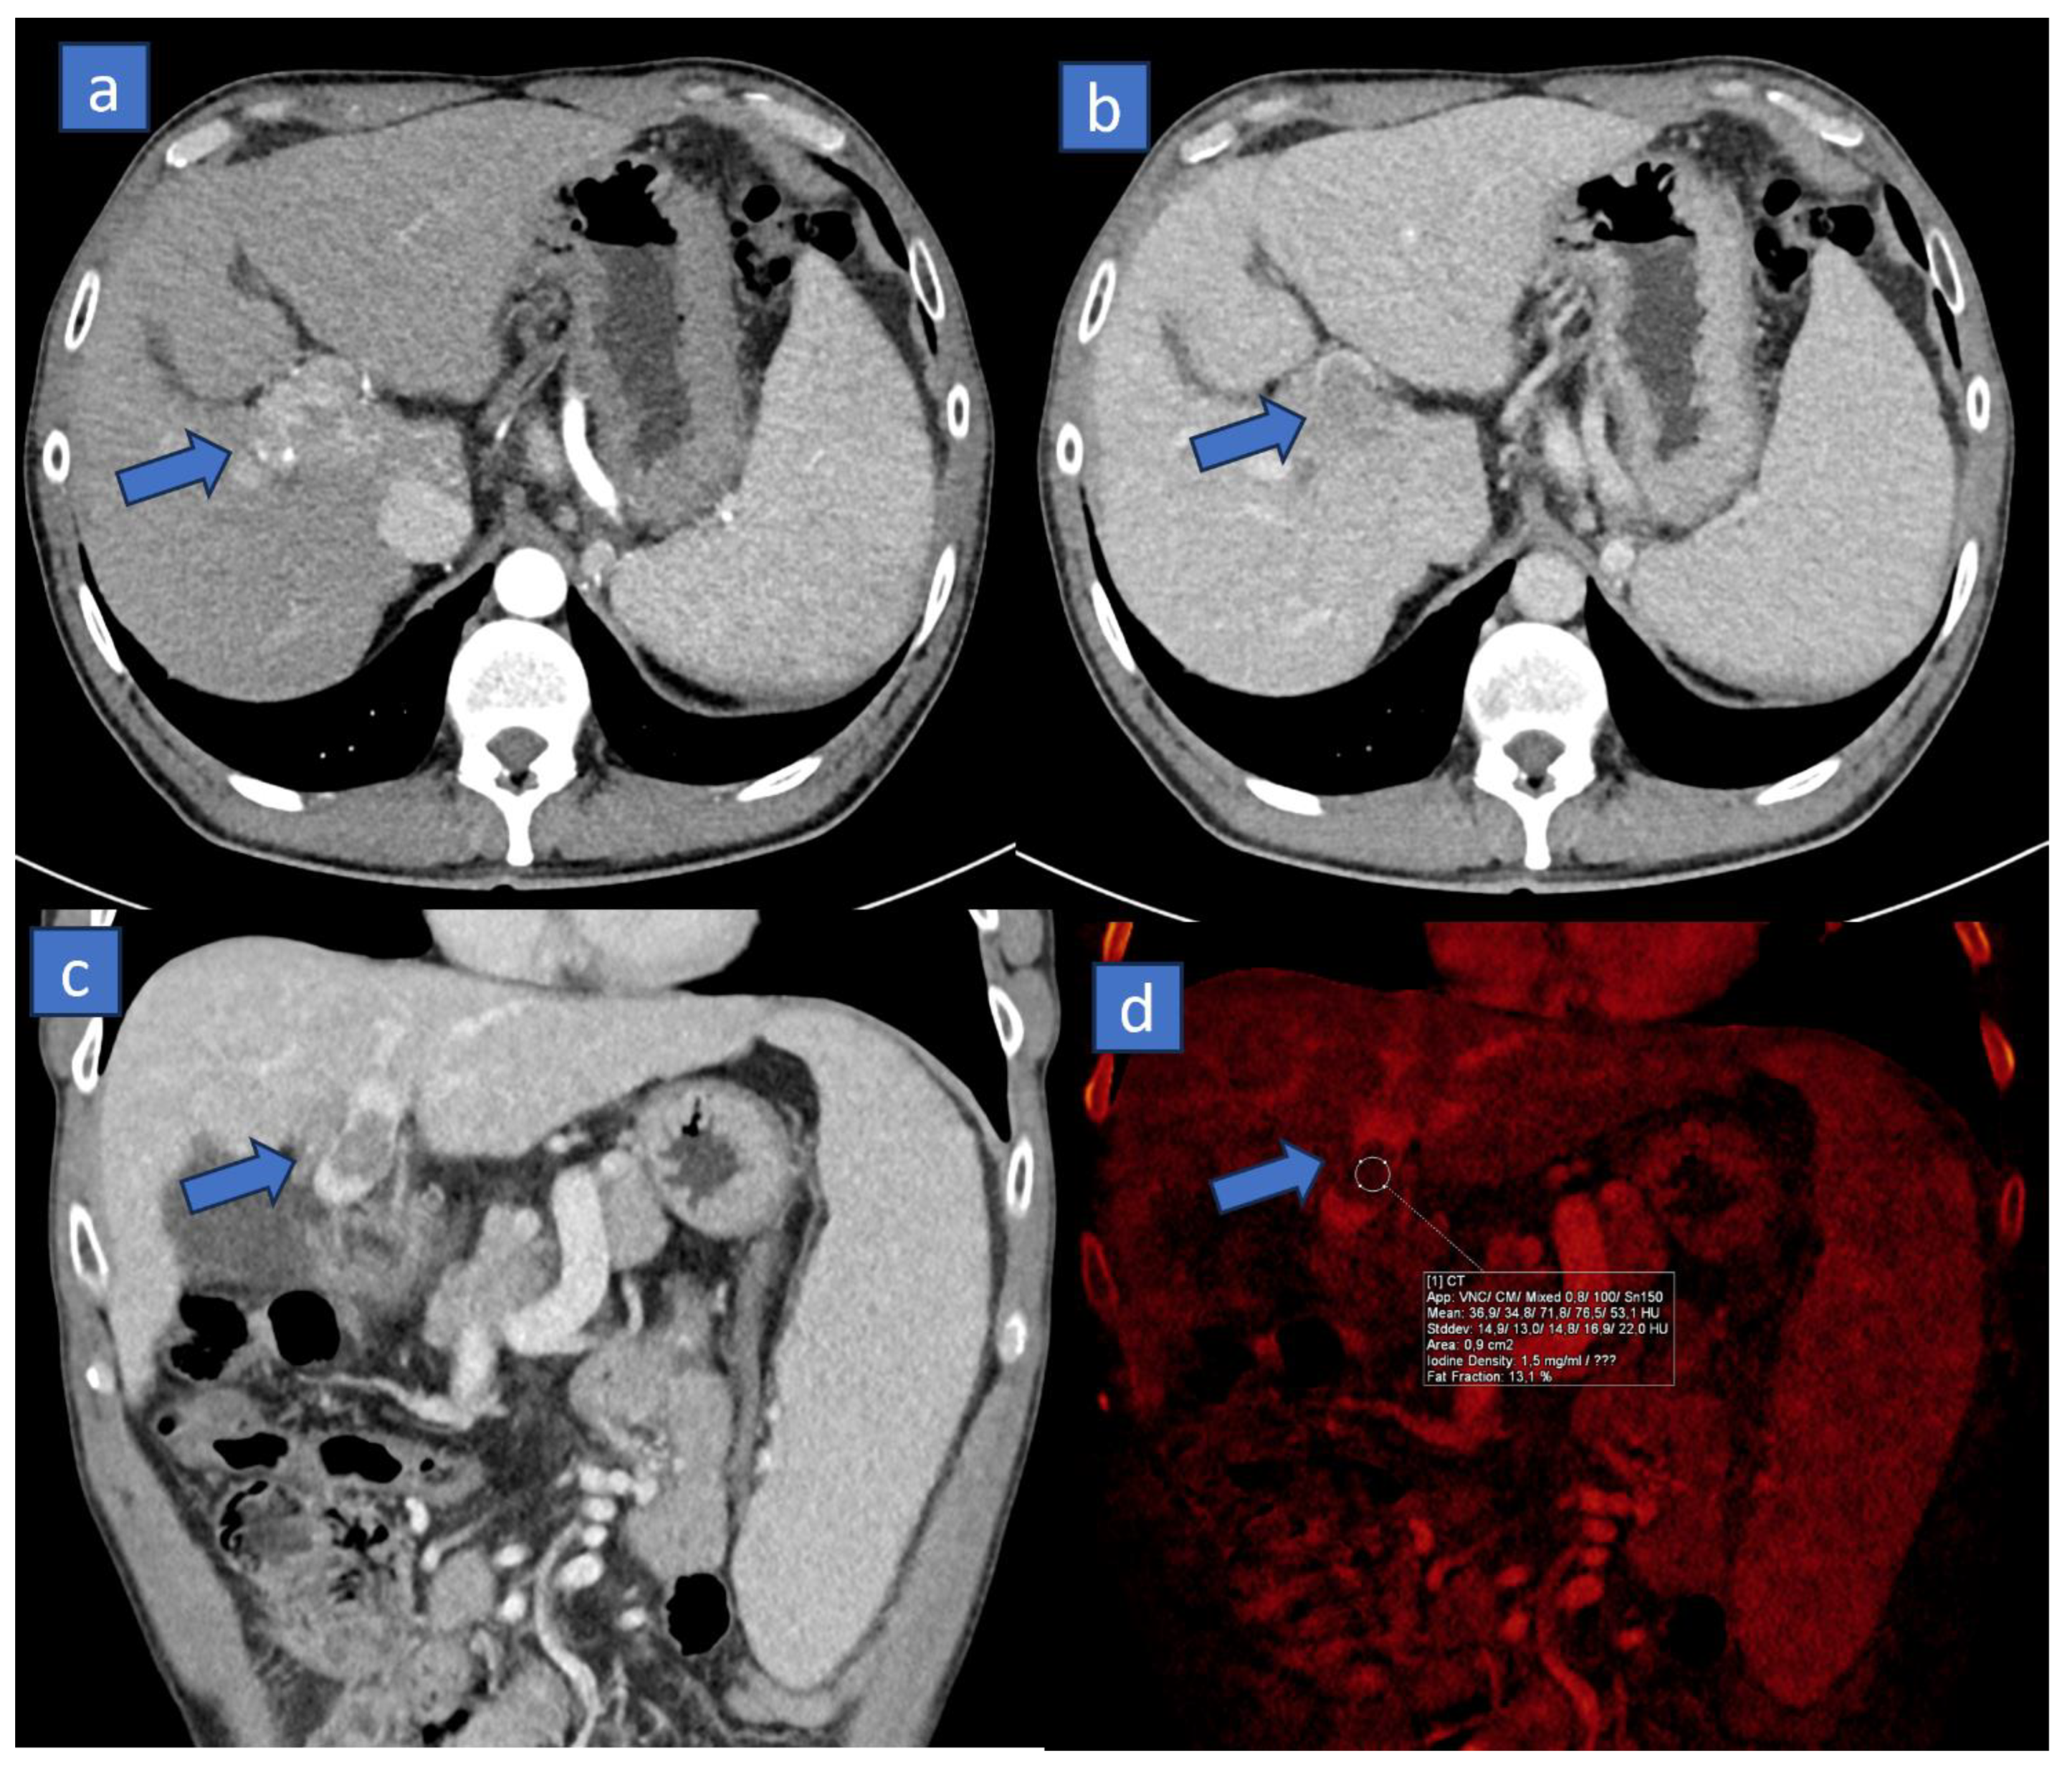

3. Iodine MAP

3.1. Applications

3.2. Response to Therapy

3.3. Organ Perfusion